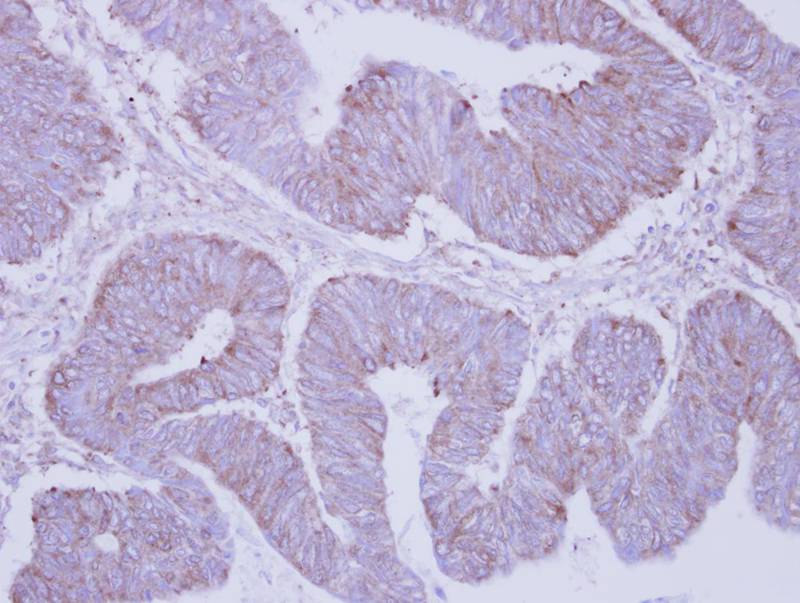

Immunohistochemical analysis of paraffin-embedded Colon ca, using PHKA2 antibody at 1: 250 dilution.